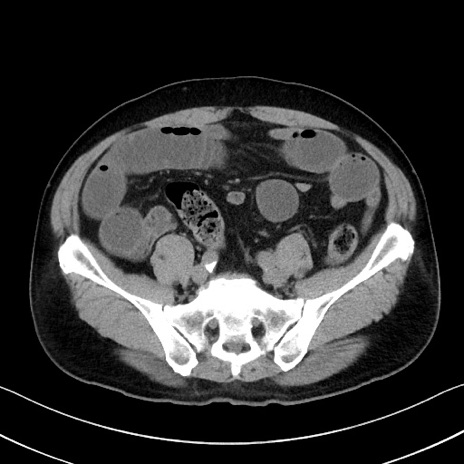

症例35(横断像)

【症例】70歳代 男性

【主訴】腹部膨満、嘔吐

【現病歴】昨日より腹部膨満感出現。本日増悪し、仙痛出現。嘔吐あり、受診。

【既往歴】糖尿病、胆摘後

【身体所見】BP 149/80mmHg、HR 74/min、BT 35.9℃、腹部:膨満、軟、圧痛なし。腸雑音減弱あり。上腹部正中切開瘢痕あり。

【データ】WBC 13500、CRP 1.72